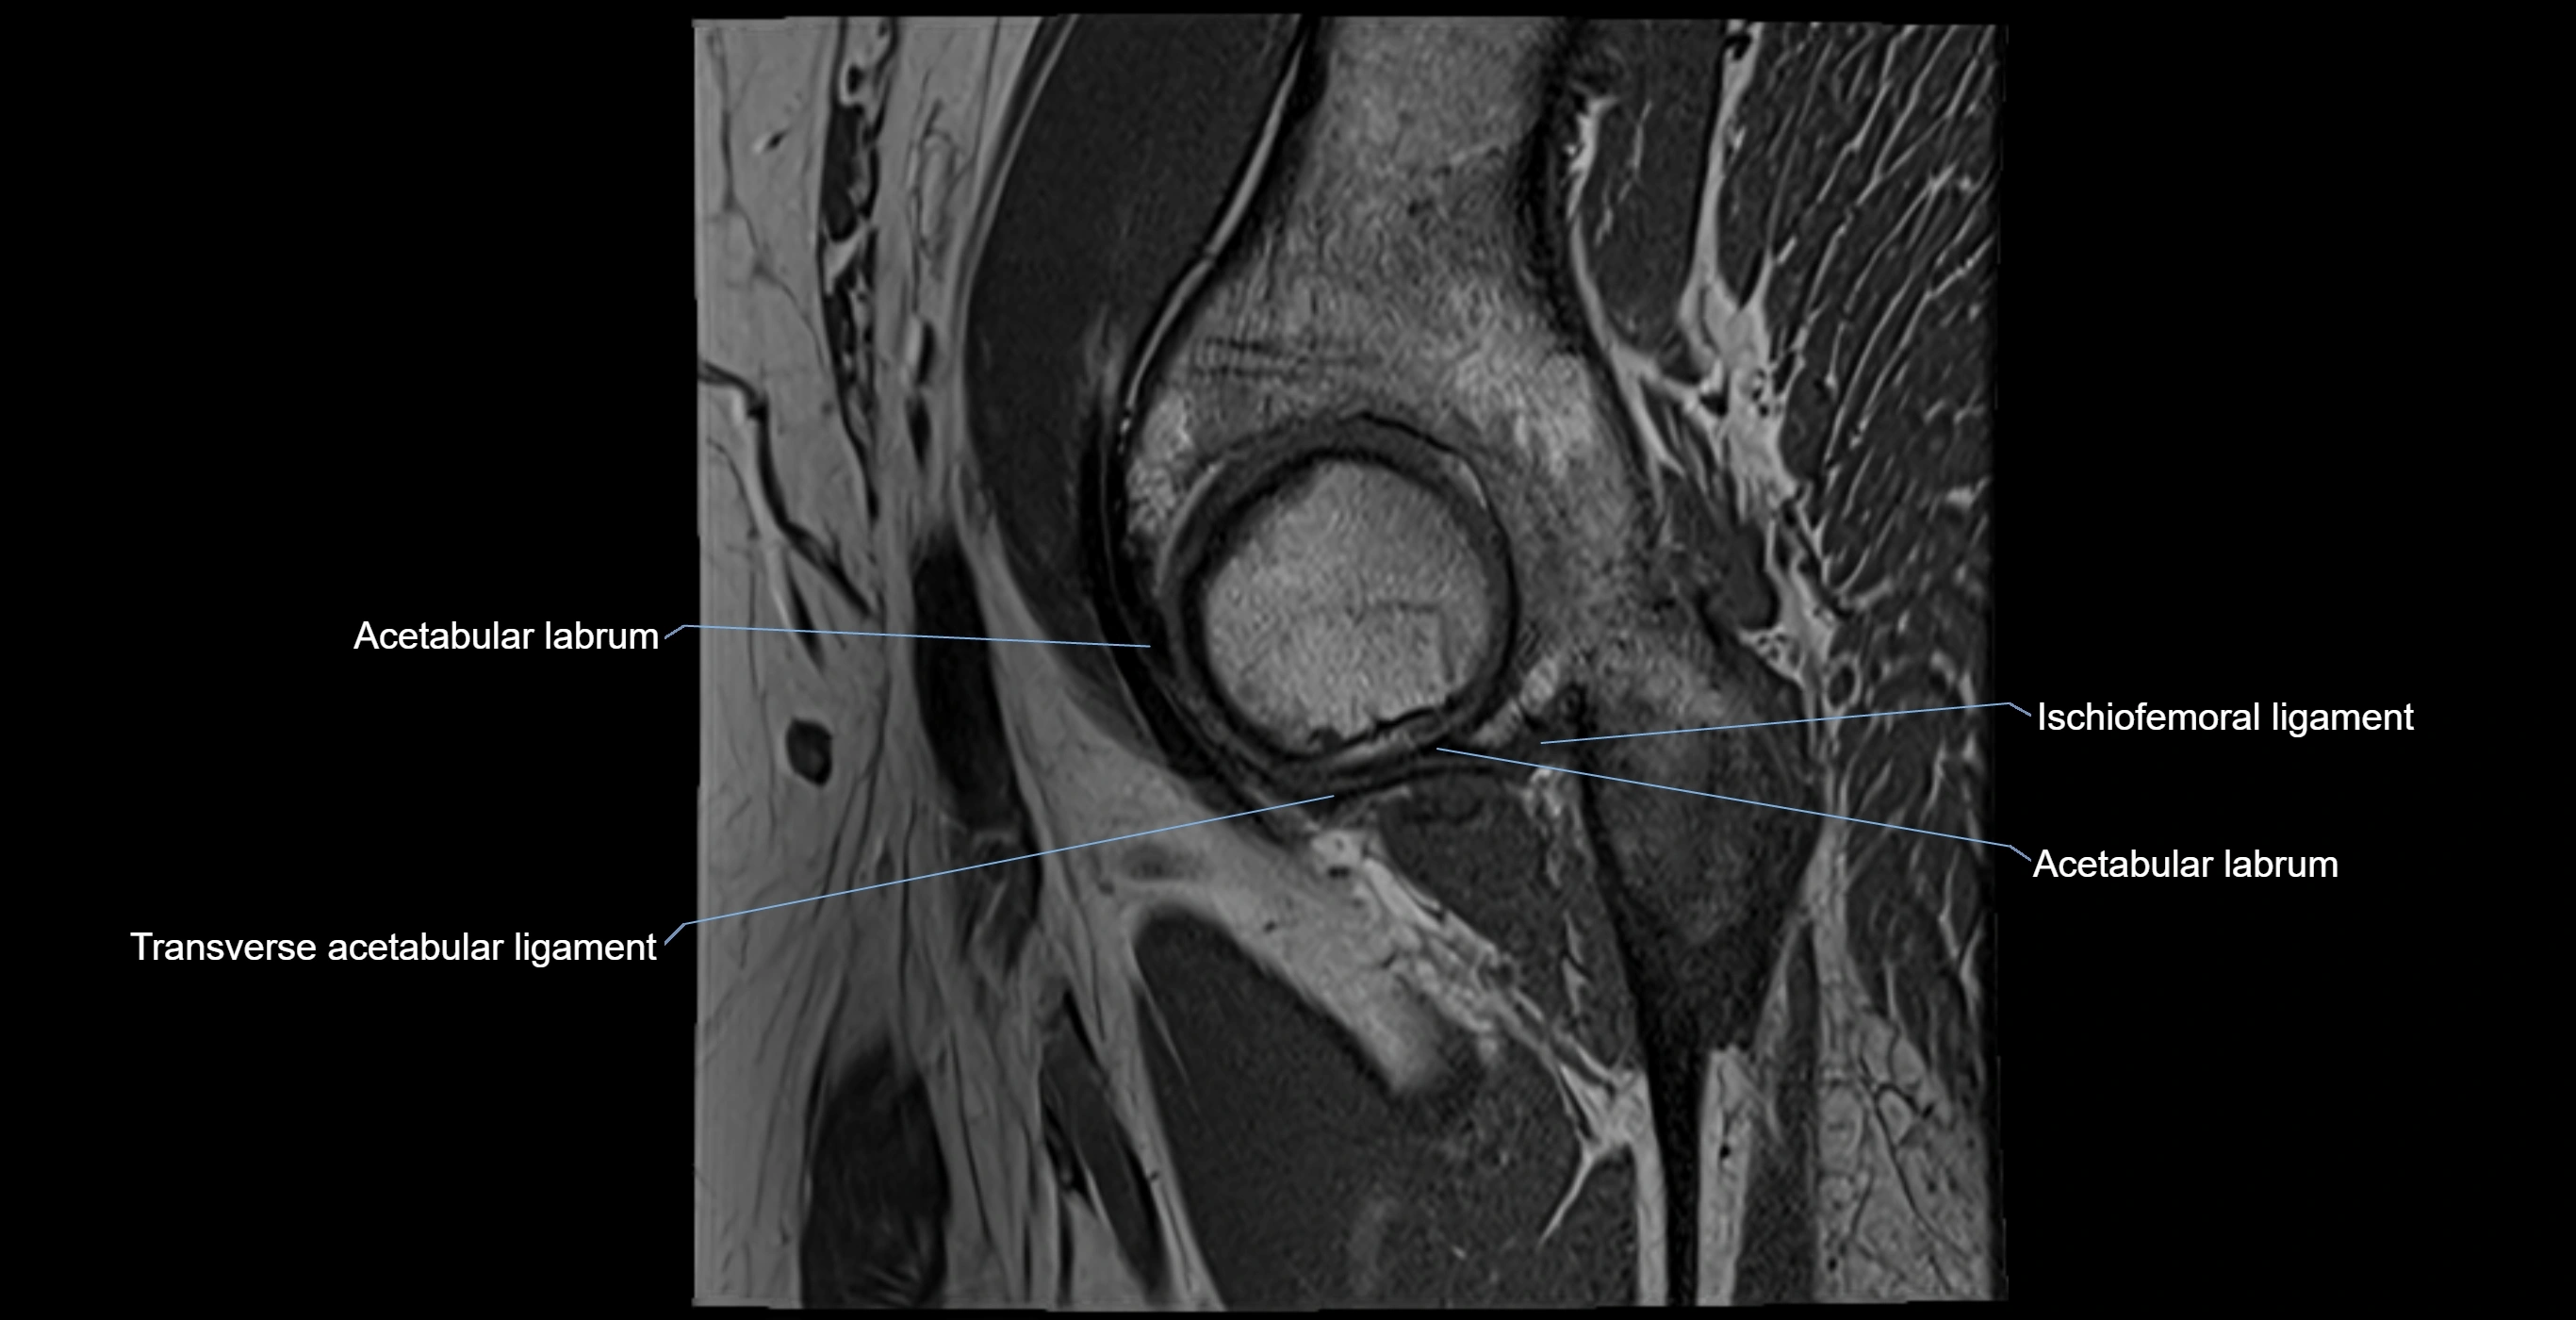

The acetabular labrum is a fibrocartilaginous ring that surrounds the rim of the acetabulum in the hip joint. It deepens the hip socket, increases joint stability, and maintains a suction seal that preserves negative intra-articular pressure. Structurally, the labrum transitions from hyaline cartilage of the acetabulum to dense fibrocartilage at its free edge.

It is triangular in cross-section, with its base attached to the acetabular rim and its apex projecting toward the femoral head. The labrum is most robust superiorly and anteriorly, where load bearing is greatest, and relatively thinner inferiorly.

Structure and Relations

• Superior and anterior labrum: thickest portions, stabilizing against anterior dislocation

• Inferior labrum: blends with the transverse acetabular ligament bridging the acetabular notch

• Inferior: transverse acetabular ligament

MRI Appearance

T1-weighted images:

• Labrum: low signal intensity (dark)

• Surrounded by intermediate signal joint fluid (bright on arthrogram)

• Tears: linear or focal areas of intermediate-to-high signal interrupting labral continuity

T2-weighted images:

• Joint fluid: bright, making labral tears visible as fluid extending into or around labrum

• Degeneration: may show areas of increased signal within labrum